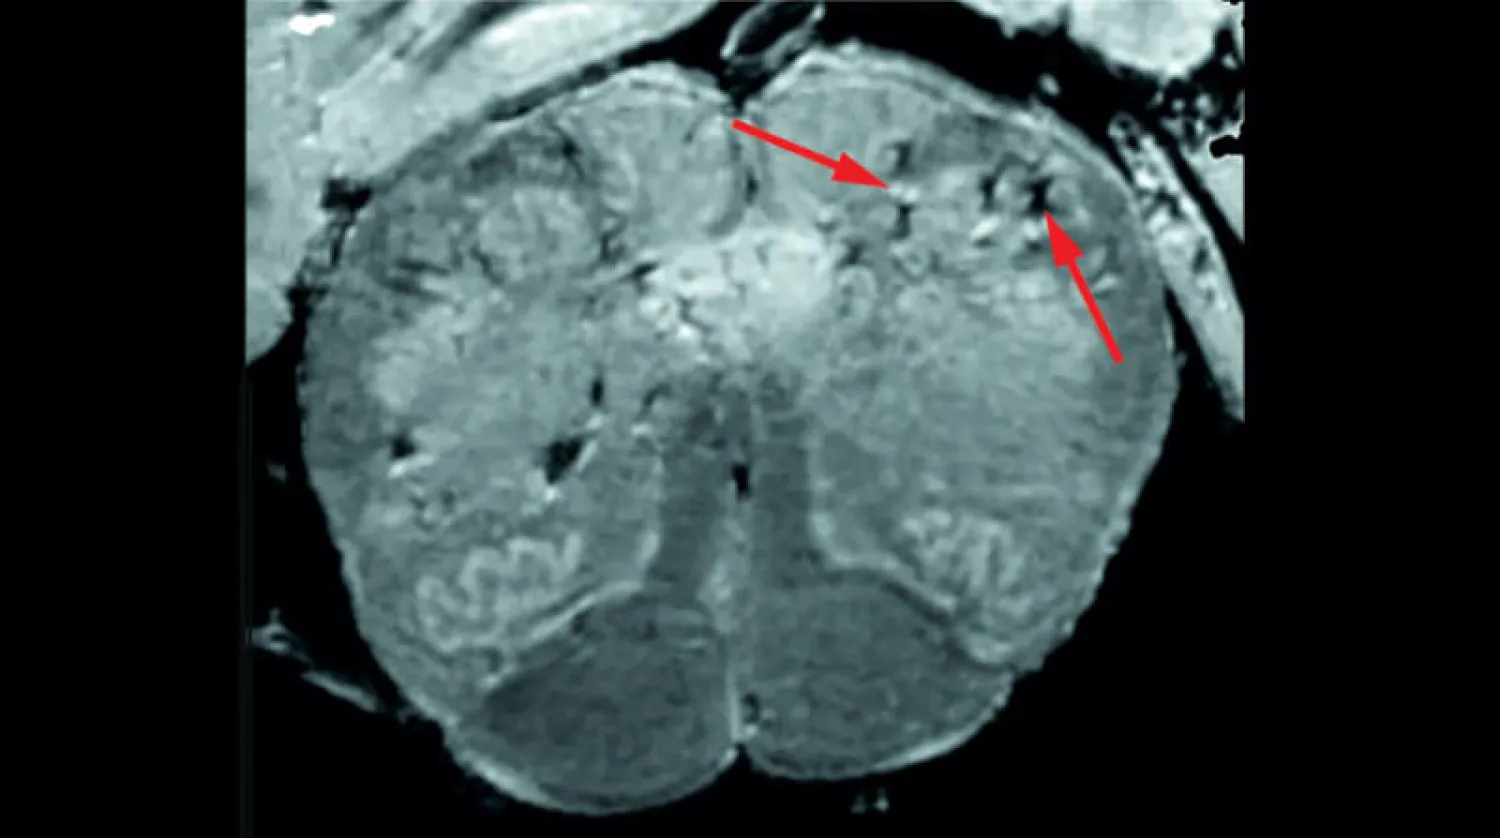

في البداية، استخدم الباحثون ماسحًا خاصًا عالي القوة للتصوير بالرنين المغناطيسي (MRI) أكثر حساسية من 4 إلى 10 مرات من معظم أجهزة التصوير بالرنين المغناطيسي، لفحص عينات من البصيلات الشمية وجذع الدماغ من كل مريض، ويعتقد أن هذه المناطق معرضة بشدة لـ«كوفيد - 19».

وتتحكم البصيلات الشمية في حاسة الشم لدينا بينما يتحكم جذع الدماغ في تنفسنا ومعدل ضربات القلب، كشفت عمليات المسح أن كلا المنطقتين بهما عدد كبير من البقع المضيئة، التي تسمى فرط الكثافة، والتي تشير غالبًا إلى الالتهاب، والبقع الداكنة، المسماة (فرط الإحساس)، التي تمثل النزيف.

واستخدم الباحثون بعد ذلك عمليات المسح كدليل لفحص البقع عن كثب تحت المجهر، ووجدوا أن البقع المضيئة تحتوي على أوعية دموية أرق من المعتاد وتسرب في بعض الأحيان لبروتينات الدم، مثل الفيبرينوجين، إلى الدماغ، ويبدو أن هذا يؤدي إلى رد فعل مناعي. وكانت البقع محاطة بخلايا تائية من الدم وخلايا مناعية للدماغ تسمى الخلايا الدبقية الصغيرة، وفي المقابل، احتوت البقع الداكنة على أوعية دموية متخثرة ومتسربة ولكن دون استجابة مناعية.

الباحثون وجدوا علامات لتلف الأوعية الدموية في المخ (المعاهد الوطنية للصحة بأميركا)